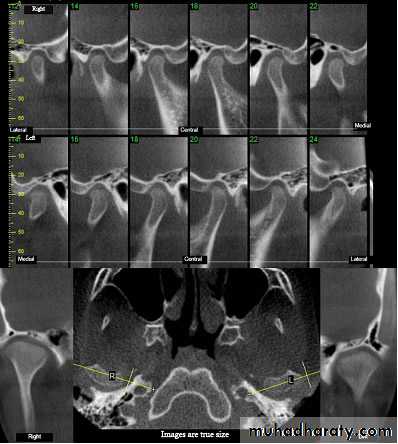

• Tomograms:

• this technique allows radiographical sectioning of the joint at deferent levels of the condyle and fossa complex which provides individual views visualizing the joint in slices from the medial to the lateral pole. these views eliminate bony super impostion, and overlap and provides a relatively clear picture of the bony anatomy of the joint.

this involves the injection of contrast material into the inferior or superior spaces of the joint after which the joint is radiographed and this well allows evaluation of the position and morphology of the articular disk and to demonstrates the presence of perforations and adhesions of the disk or its attachments.• Computed tomography:

provides evaluation of a variety of hard and soft tissue pathology in the joint which can be done from a single radiation exposure. + CT images provide the most accurate radiographic assessment of the bony components of the joint• magnetic resonance imaging: